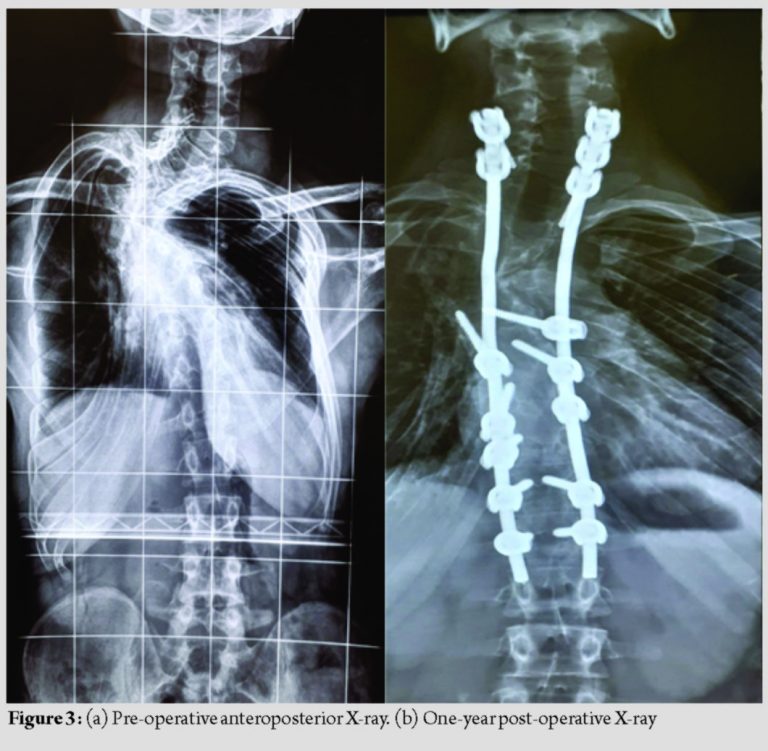

Copious amounts of morselized autologous bone graft were placed posteriorly to promote posterior bony fusion. Time for surgery was 4.5 h. Blood loss was 800 ml. There were no intraoperative adverse events. The post-operative period was uneventful. Kyphosis was corrected from 100° to 65° and scoliosis (Coronal Cobbs angle) was corrected from 100° to 60°. The patient was back to full functional status. At 1-year follow-up, good fusion was achieved, as seen on the X-ray (Fig. 3a and b and 4a and b).

There was no coronal or sagittal imbalance at end of 1 year and upper back hump was cosmetically better compared to pre-operative (Fig. 5a and b) (Fig. 6a and b).

NF-1 is an autosomal dominant disorder. Scoliosis is seen in about 10–64% of NF-1 [1,3]. The prevalence of NF-1 is 1:3000 [8,9]. Curves are dystrophic or non-dystrophic type. Non-dystrophic curves usually present like idiopathic scoliosis [10]. Tsirikos et al. [11] reported that dystrophic curves <20° should be closely observed and a sudden progression in the curve should be considered for surgery. Dystrophic curves more than 20° generally require surgery. The approach for surgery in such patients remains unresolved. The choice is between a combined anterior plus posterior fusion and an all posterior fusion. Kim and Weinstein [12] believed that dystrophic scoliotic curves of 20–40° and kyphosis <50° can be managed with posterior spinal instrumented fusion only. To obtain better correction and avoid pseudoarthrosis, anteroposterior fusion was recommended when dystrophic scoliosis was greater than 40° and/or kyphosis was greater than 50°. The efficacy of anterior surgery is often compromised due to hyperkyphosis and vertebral rotation according to some authors [3,13]. The presence of tumor or excessive plexiform venous channels around the vertebral bodies sometimes makes it impossible to approach the apex of the curve anteriorly. Due to dystrophy, apical vertebrae can be significantly subluxated and malaligned from rest of the spine. Such malalignment does not allow anterior strut grafts to be placed in the concavity of the kyphosis, and hence, they are mechanically ineffective in preventing its progression [14]. Some authors have described the use of pre-operative halo gravity traction, especially in rotatory subluxation of vertebrae in NF-1 dystrophic curve to minimize risk of correction surgery, improve flexibility of the curve and pre-operative pulmonary function [6,7]. We concluded that pre-operative traction in such a patient may not be as effective in distracting the apex of the deformity as there was partial fusion observed at the apex of the deformity, especially the D5-D6 vertebra. In our opinion, the purpose of surgery in these cases is to stabilize the vertebral column and halt further progression of deformity rather than aiming for full correction of the curve. We believe that kyphosis correction through the anterior approach would have been difficult, in such a lesion in the upper thoracic spine due to the deep, high apex, and crowding of the vital structures around this region. We also observed in the radiological investigations that the dysplastic vertebra of D5 was posteriorly sequestered with the vertebra of D4 and D6 partially covering it anteriorly. In our opinion, the access to the D5 vertebra in such a situation would have been less than adequate anteriorly, leading to the possibility of incomplete excision of the D5 vertebra and the posterior bony knuckle caused by it. According to the recently published guidelines of management of kyphosis by Rajasekaran et al., this patient was considered to be a Type III B type of kyphosis [15]. The authors recommended doing a posterior vertebrectomy and posterior fixation with or without a pre-operative halo gravity traction. Keeping in mind the aim of our surgery to stabilize the kyphosis and prevent further progression of the deformity, along with removing the offending bony knuckle of the D5 vertebra causing the pressure on the cord, we chose to do a three column osteotomy at the apex D5 level and posterior fixation from C7 to T2 and T8-L1 fixation along with titanium rods. We did not excise the whole of the D5 body, but left behind the endplates of the D5 body, on which the osteotomy was closed. This we chose to do keeping in mind the higher rates of pseudoarthrosis in NF-1. We tried to eliminate the need of a metallic mesh cage with autologous bone graft and instead chose to keep the native bone to bone contact and augmented the posterior fusion bed with the remaining autologous bone. We managed to achieve an acceptable kyphosis correction from 100° to 65° and scoliosis correction from 100° to 60°. These measurements remained same at the end of 1 year follow-up with a good fusion status, as seen on the X-ray. There was excellent cosmetic improvement of the upper back deformity and no further progression of the myelopathy in the patient. The limitations of this report are the short period of post-operative follow-up and lack of documentation of the fusion status by a CT scan. We usually avoid doing regular CT scans on our patients when we observe on the X-ray that there is no implant loosening, loss of correction, or progression of the deformity.